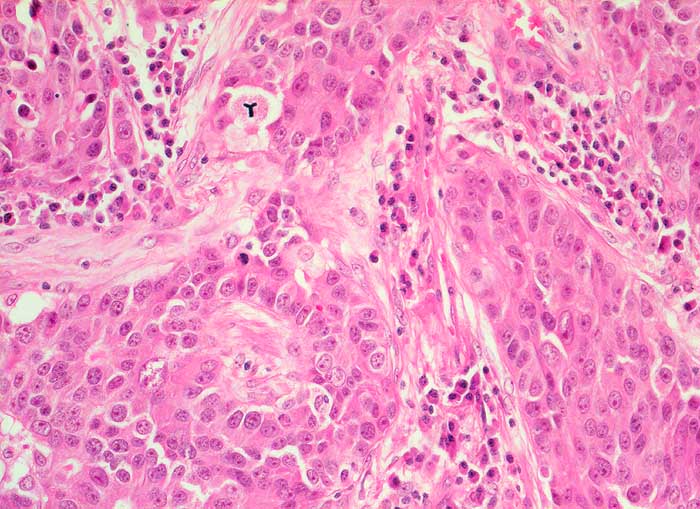

Gezeigt werden Beispiele von Metastasen eines Mammakarzinoms, eines Nierenzellkarzinoms, eines malignen Melanoms und eines Seminoms.

Mammakarzinomzellen im Bronchialsekret liegen oft dicht vermischt mit Flimmerzellen, was auf eine Lymphangiosis carcinomatosa hinweist. Die wenig atypischen Tumorzellen sind dabei kaum von den Zellkernen der Flimmerzellen zu unterscheiden.

Die runden Kerne des hellzelligen Nierenzellkarzinoms enthalten einen auffallenden grossen Nukleolus, das Kernchromatin ist fein granulär und hell. Das Zytoplasma ist vakuolisiert und blass.

Melanomzellen liegen einzeln oder in pseudoepithelialen Verbänden. Pigmentgranula und plumpe sehr grosse Nukleolen weisen auf das Melanom hin.

Die Tumorzellen von Keimzelltumoren besitzen ebenfalls meist auffallende Nukleolen. Seminomzellen sind quetschempfindlich und zytoplasmaarm.